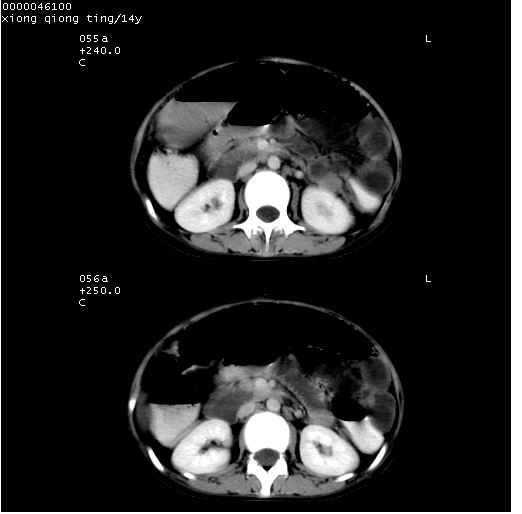

中下腹及盆腔ct轴位平扫+增强扫描(层厚10mm,螺距1.0,重建间隔10mm),图像如下:

(注:患儿检查当日上午9时口服胃肠道对比剂,下午3时许行ct扫描检查,未行对比剂直肠保留灌肠,检查当日患儿腹泻)

中下腹及盆腔ct轴位扫描(ps+ce)提示:腹部肠管明显充气扩张,并见数个不同宽度之气液平面;疑不全性肠梗阻或肠郁张。临床会诊考虑为患儿腹泻,肠郁张所致;后来未经特殊处理,患儿大便恢复正常,亦无腹胀。